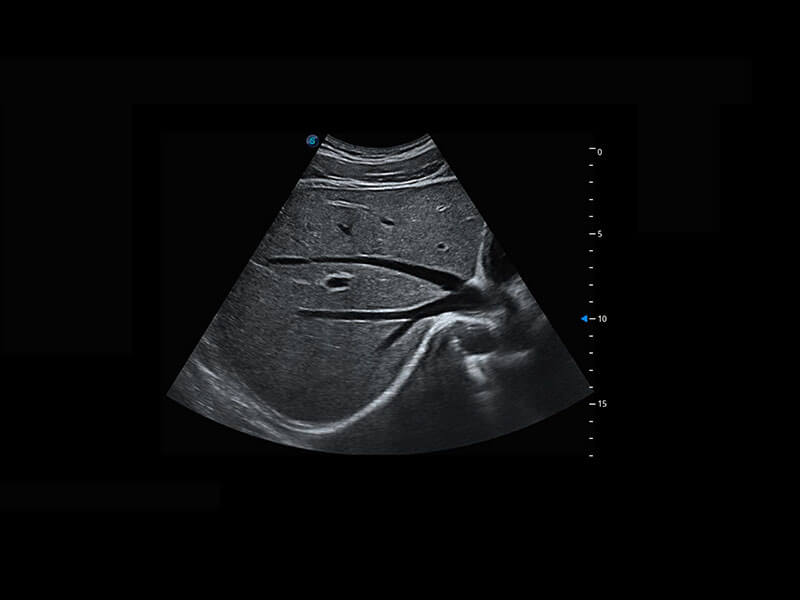

P60为盆底超声检查提供应用方案,多种腔内及腹部容积探头提供从二维、三维到四维的优异图像品质,实时快速三维容积数据获取,专业的测量工具包等人性化设计,为超声医生诊断提供有力保障。

Lev.Hiat A-r: 16.33 cm2

Lev.Hiat H-r: 53.70 mm

Lev.Hiat W-r: 43.96 mm

Lt-LUG-r: 24.16 mm

Rt-LUG-r: 19.94 mm

能够简化盆底检查的操作流程,可在二维模式及三维成像模式下实现一键自动提取出标准切面、自动识别当前切面、自动测量,提升盆底检查的高效性,同时也能让青年医生快捷的获得准确的检查结果。